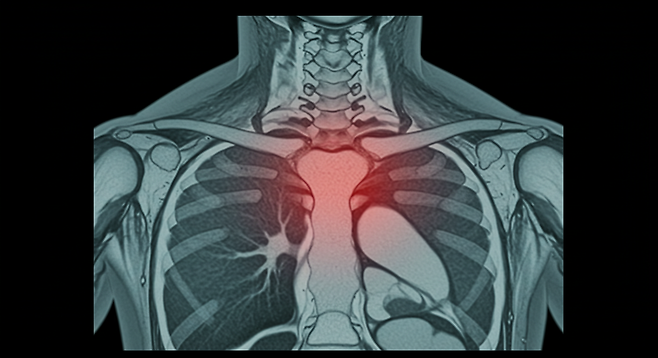

늑연골염은 갈비뼈와 흉골(가슴뼈)을 연결하는 연골에 발생하는 염증입니다. 티체 증후군(Tietze syndrome)이라고도 불리는 이 상태는 심장 질환과 유사한 통증을 유발할 수 있어 정확한 진단이 중요합니다.

- 특히 흉골과 갈비뼈가 만나는 부위에서 압박감

늑연골염은 주로 임상적 증상을 바탕으로 진단되며, 다른 심각한 원인을 배제하기 위해 심전도, X선, CT 또는 MRI 검사가 필요할 수 있습니다.